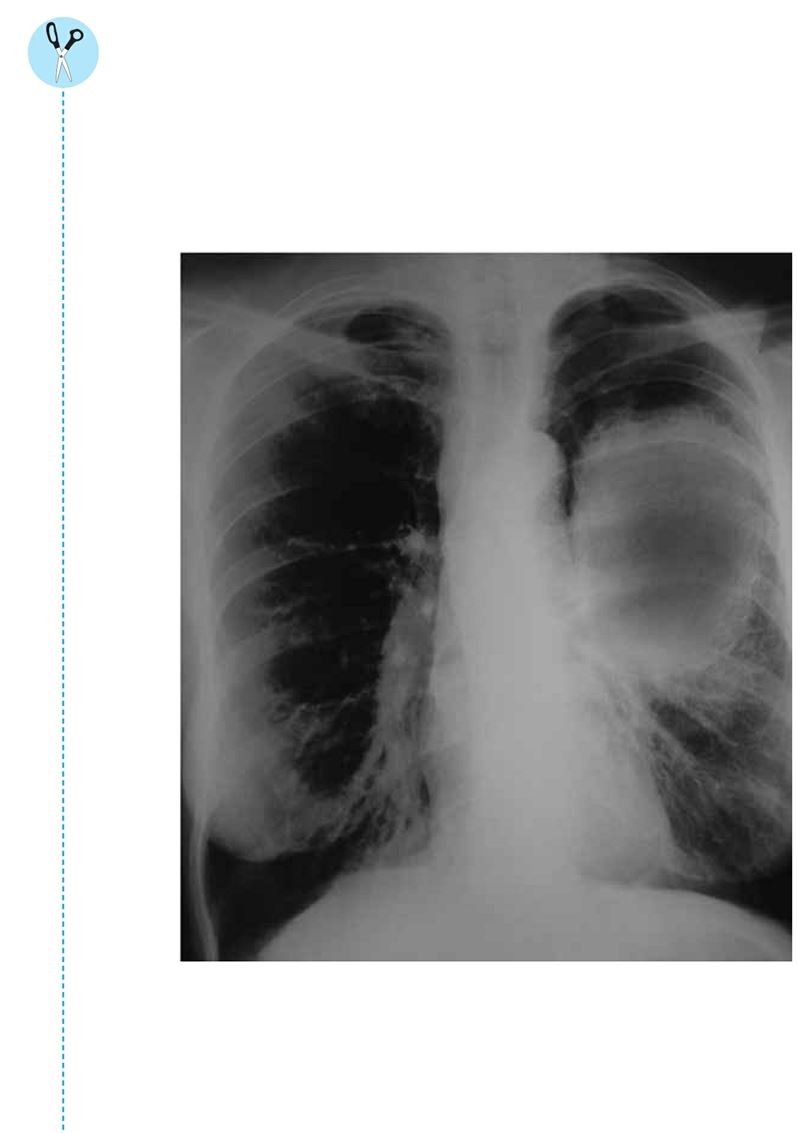

此外,香烟中含有一些有毒的化学物质,可能导致肺癌。医生使用X光检测病人是否患有肺癌。在X光片中,黑色的部分表示X光没有受到阻碍,白色的部分则表明X光遇到了一些障碍物,如致密组织或骨骼。

上一页是一张X光片,其中该病人左侧肺部患有癌症。此人60出头,这辈子吸烟成瘾,每天都抽很多支烟。他的肺部有大量的伤疤以及癌细胞,就是X光片上这些白色的组织。肺癌的后果是非常可怕的。比方说,癌细胞直径超过1英寸的患者,即使接受最有效的治疗,也只有不到一半的人能活过五年。像这个病人,根据他的X光片情况,也许他活不过一年。

你吸烟多久了?你是不是已经感到呼吸困难了?你是不是有一些健康问题?如果你继续吸烟,很可能几年后你的X光片就会和这位病人一样了。你对此感觉如何?想想看,这会给你自己以及你身边的人带来怎样的影响?